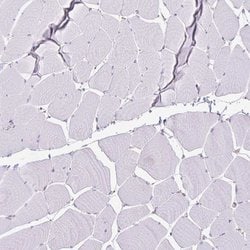

| Immunohistochemistry (Paraffin), Immunocytochemistry | |